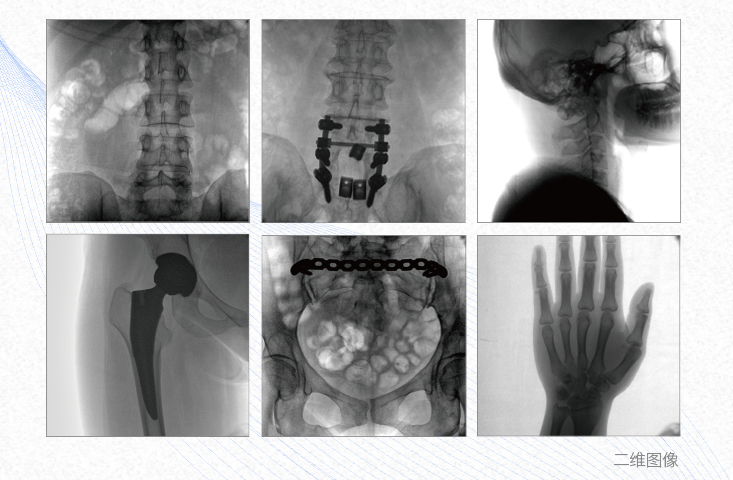

有效重建復(fù)雜的脊柱三維模型,提供準(zhǔn)確的二維、三維圖像,提高螺釘植入的準(zhǔn)確性,縮短手術(shù)時(shí)間,減少并發(fā)癥的概率,降低輻射的攝入。

例如骨盆骨折內(nèi)固定術(shù),可術(shù)中三維重建髖臼關(guān)節(jié)面,準(zhǔn)確定位并植入螺釘,有效縮短螺釘植入的時(shí)間和透視暴露時(shí)間,減少術(shù)中及術(shù)后并發(fā)癥發(fā)生的概率。

主要應(yīng)用于肩關(guān)節(jié)、肘關(guān)節(jié)、髖關(guān)節(jié)、膝關(guān)節(jié)的關(guān)節(jié)置換及解剖復(fù)位的定位。它可以準(zhǔn)確地置入假體,減少輻射時(shí)間,降低輻射劑量。

例如治療先天性脊柱側(cè)后凸畸形,可有效引導(dǎo)術(shù)者植入后路螺釘并切除半錐體,達(dá)到滿意的截骨矯正效果。

術(shù)中三維成像和橫斷面圖像提供多角度的手術(shù)診斷信息,輔助醫(yī)生進(jìn)行術(shù)中評(píng)估判斷,諸如骨折復(fù)位情況和內(nèi)植入螺釘?shù)某叽绾臀恢茫o助手術(shù)更好地完成。

提供更大的術(shù)中三維成像視野,采集更多圖像信息,可一次拍全全段頸椎、全段腰椎、七節(jié)胸椎、雙側(cè)骶髂關(guān)節(jié)、股骨頭及單側(cè)盆骨。